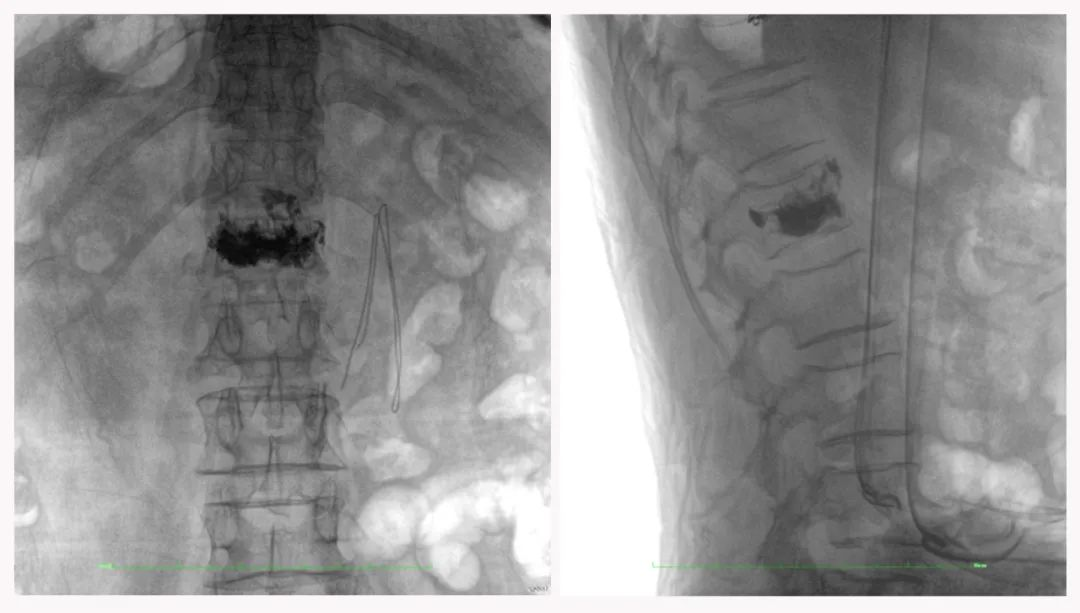

病例3:超聲支氣管鏡下肺活檢(80歲)

三維C形臂還可以創(chuàng)新性地應(yīng)用在呼吸介入領(lǐng)域。例如,在經(jīng)皮穿刺或經(jīng)支氣管鏡肺結(jié)節(jié)活檢、定位、消融等場景中,用于確認(rèn)工具是否到達(dá)病灶、消融范圍是否完全覆蓋病灶等。

二維影像無法準(zhǔn)確判斷工具是否到達(dá)病灶

三維各切面影像都顯示工具達(dá)到病灶內(nèi)

二維C形臂提供的影像存在固有局限性,其成像原理是基于單一方位的投影,導(dǎo)致深部解剖結(jié)構(gòu)信息缺失,且容易受到骨骼和組織的重疊干擾,使得部分病灶難以清晰顯示,甚至被掩蓋。相比之下,三維C形臂通過三維重建技術(shù),可以獲得類似CT的斷層掃描圖像,從而解決了二維影像的重疊問題。

醫(yī)生能夠利用這些三維圖像,更直觀、更深入地分析病變,進(jìn)行全方位觀察,例如:精確評估骨折復(fù)位情況、清晰顯示內(nèi)植入物的位置及其與周圍組織的關(guān)系等。尤其在復(fù)雜骨折、脊柱手術(shù)、呼吸介入等臨床場景中,三維C形臂提供的詳細(xì)信息對手術(shù)導(dǎo)航和療效評估至關(guān)重要。